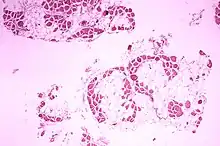

| Microscopic image of cross-sectional calf muscle from a person with Duchenne muscular dystrophy, showing extensive replacement of muscle fibers by fat cells. | |

Duchenne muscular dystrophy causes progressive muscle weakness due to muscle fiber disarray, death, and replacement with connective tissue or fat.[3] The voluntary muscles are affected first, especially those of the hips, pelvic area, thighs, calves.[3][2][12] It eventually progresses to the shoulders and neck, followed by arms, respiratory muscles, and other areas.[12] Fatigue is common.[13]

A classic sign of Duchenne muscular dystrophy is trouble getting up from a lying or sitting position,[17] as manifested by a positive Gowers's sign. When a child tries to rise from lying on his stomach, he compensates for pelvic muscle weakness through the use of the upper extremities:[15] first by rising to stand on his arms and knees, and then "walking" his hands up his legs to stand upright. Another characteristic sign of Duchenne muscular dystrophy is pseudohypertrophy (enlarging) of the muscles of the tongue, calves, buttocks, and shoulders (around age 4 or 5). Fat and connective tissue eventually replace the muscle tissue, hence the term pseudohypertrophy. Muscle fiber deformities and muscle contractures of Achilles tendon and hamstrings can occur, which impair functionality because the muscle fibers shorten and fibrose in connective tissue.[12] Skeletal deformities can occur, such as lumbar hyperlordosis, scoliosis, anterior pelvic tilt, and chest deformities. Lumbar hyperlordosis is thought to be a compensatory mechanism in response to gluteal and quadriceps muscle weakness, all of which cause altered posture and gait (e.g.: restricted hip extension).[19][20]